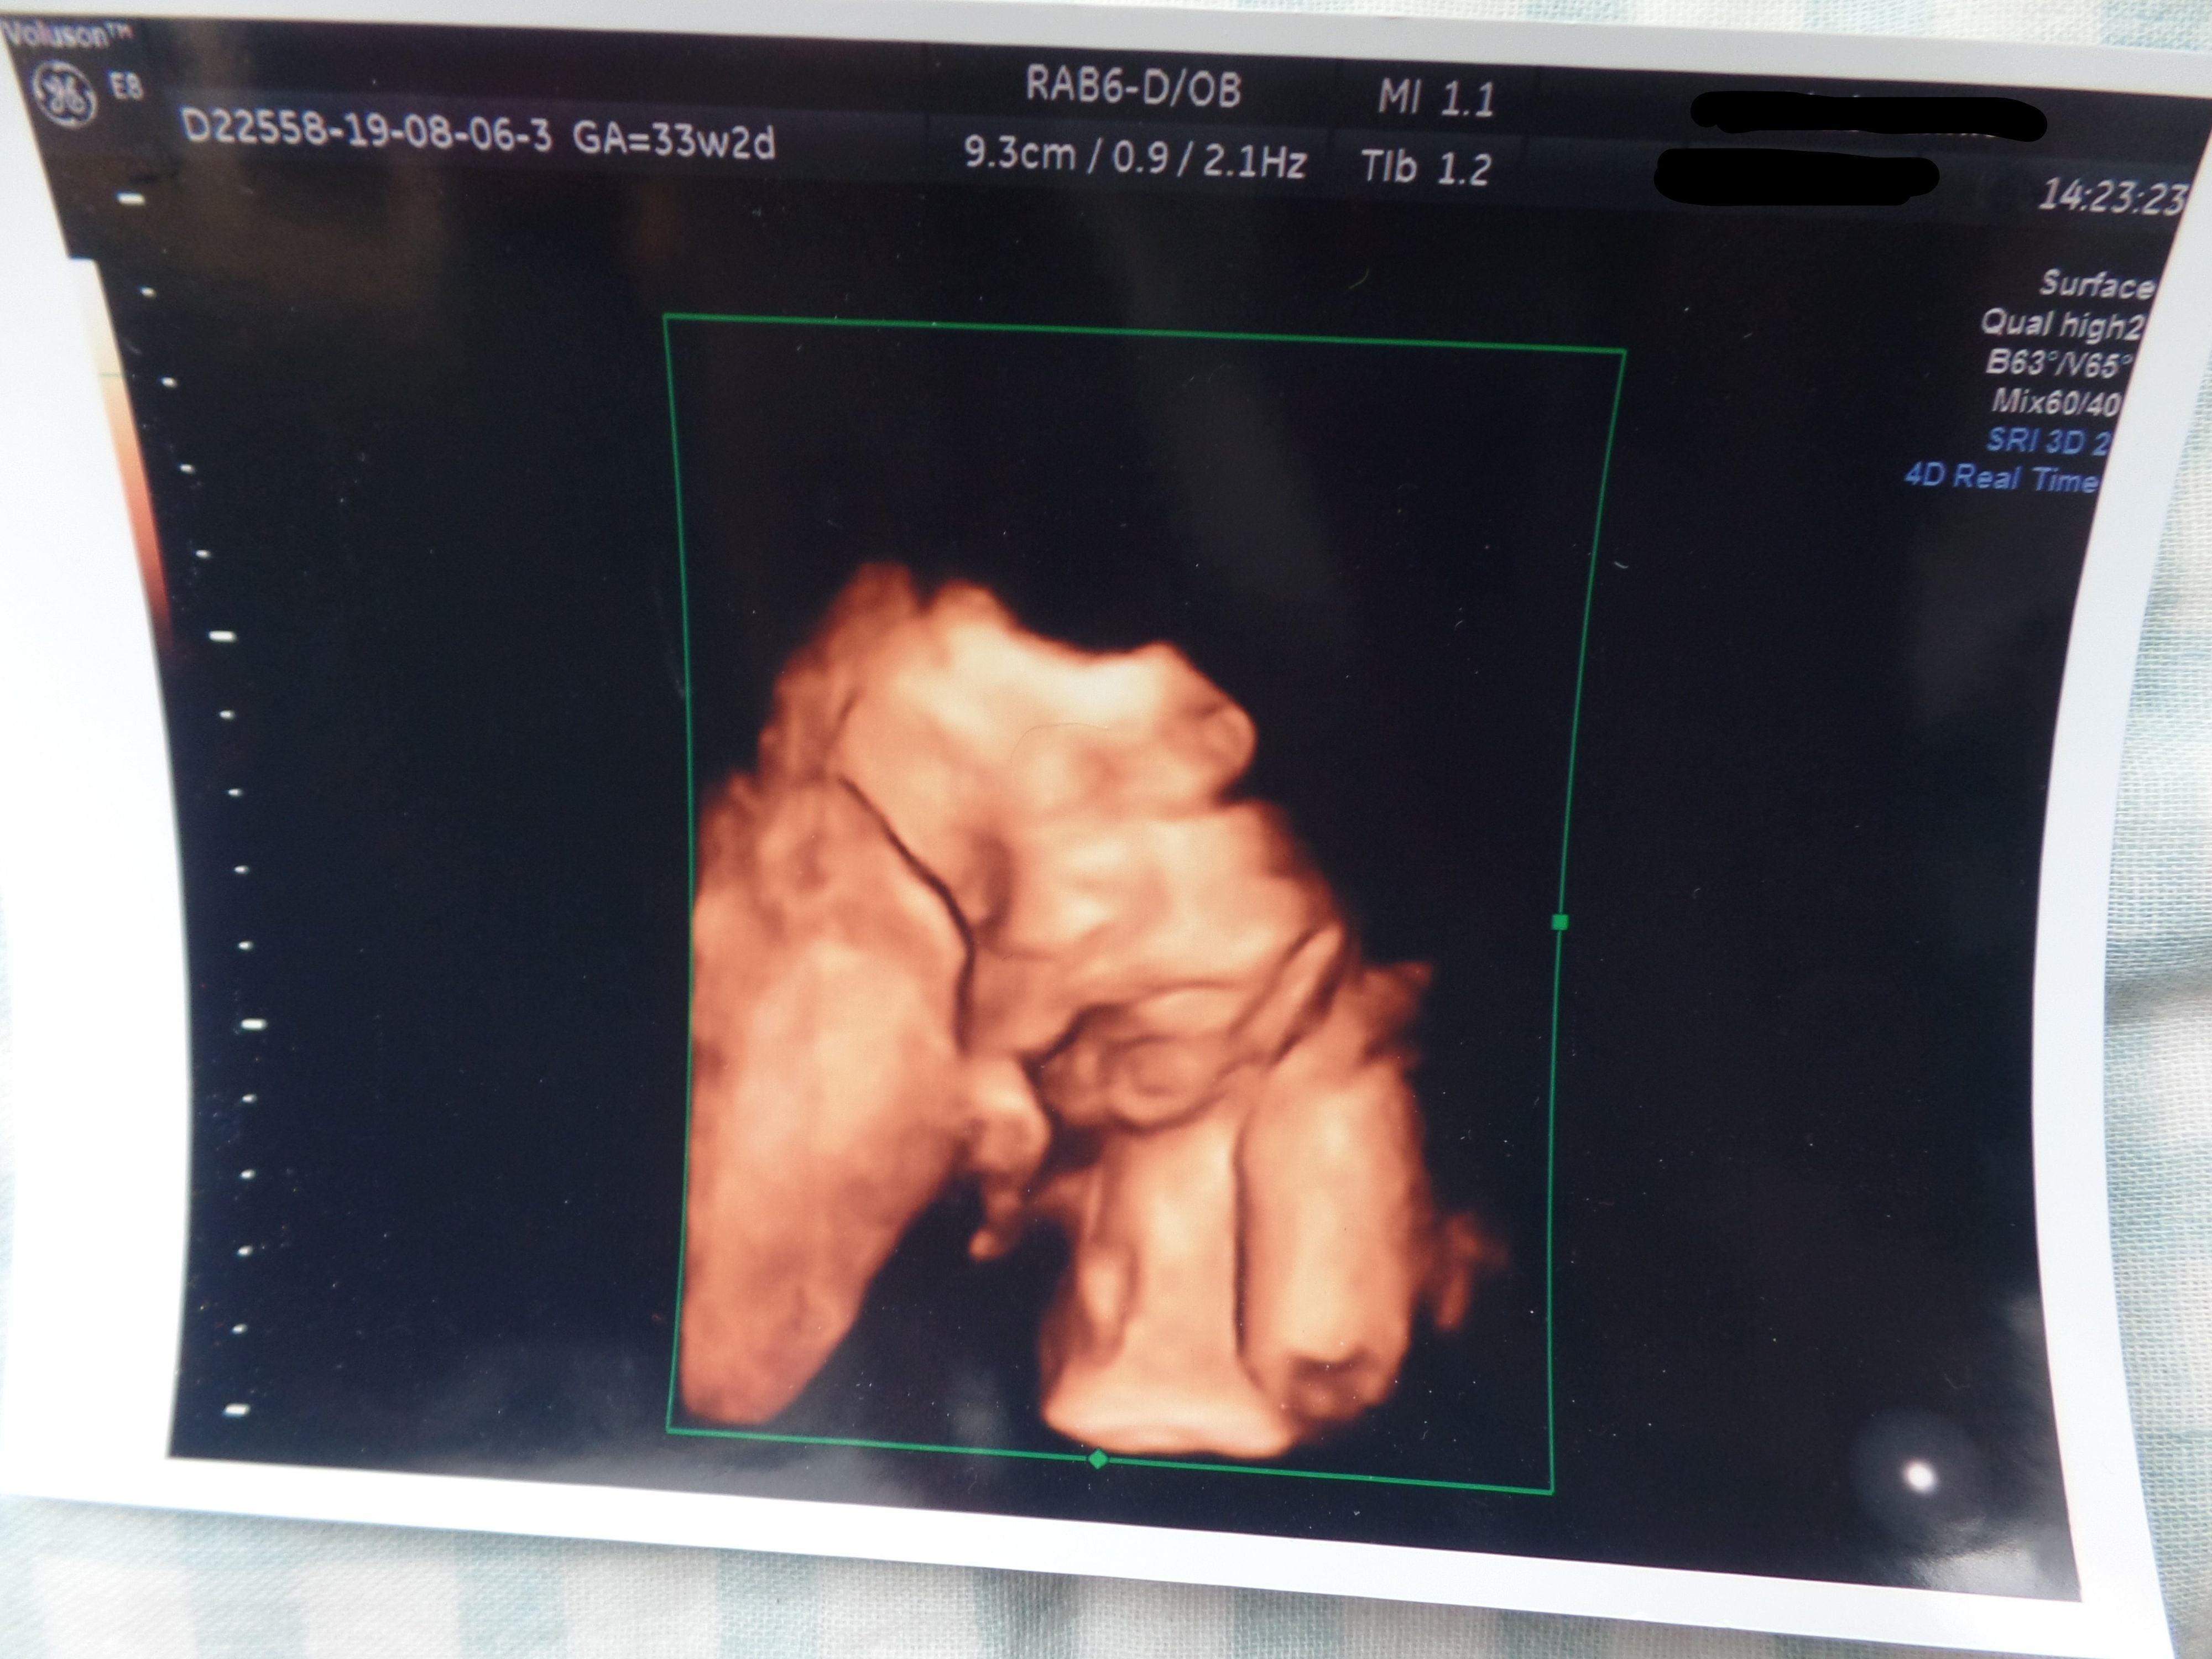

3. 多嚢胞性卵巣症候群(PCOS)から不妊治療を経て高齢出産! エコー写真で喜びを振り返る